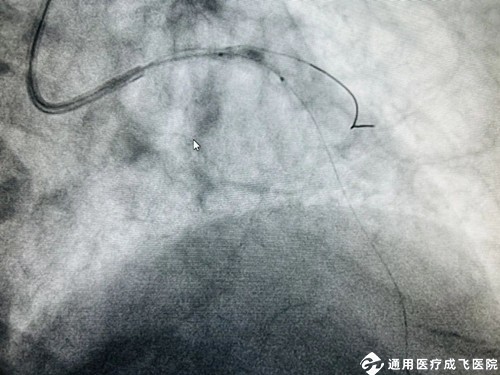

手术中,在王勉教授的指导下,心内科介入团队采用Shockwave 震波技术通过先后触发7个周期(70个脉冲)反复冲击波,以局部高效的震荡形式,对血管内的钙化结构进行“敲打”,在不影响正常血管组织的情况下将钙化结构碎裂,从而打开血管的“紧箍咒”,使血管扩张开,为后续的支架植入和充分扩张提供条件。术中前降支-左主干成功植入长支架1枚,历时仅1小时,病变狭窄明显缓解,管腔面积得到有效恢复,血流通畅。任大爷各项生命体征平稳,一直萦绕心头的“顽石”落了地,择期即将出院。

术中,振波球囊